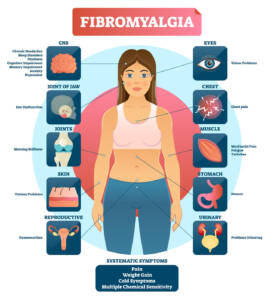

Nella Fisiatria: ottimo nella riabilitazione neuromotoria e nella fibromialgia.

artrosi,

processi infiammatori cronici, dolore cronico,

Nella Neurologia: la terapia è particolarmente valida nelle cefalee vascolari e tensive,

nella depressione di tipo lieve,

nelle malattie neurovascolari, nella sindrome da affaticamento cronico

e nelle patologie cerebrovascolari.

Nella Neurochirurgia: ottimi risultati vengono apportati in caso di ernia del disco,

dolore lombare e cervicale e lombosciatalgia.

Nell’Ortopedia: ottimi risultati sono stati riscontrati nel reumatismo articolare,

nella gonartrosi, nella protrusione discale e nella coxartrosi.

Trova anche indicazione nel trattamento di malattie a carico di piccole e grandi articolazioni.

Nelle malattie degenerative: per il trattamento di sclerosi multipla,

SLA,

Parkinson

e demenza senile precoce.

Ottima per disturbi muscolo scheletrici come ernia del disco, tunnel carpale,

gomito del tennista,

periartrite della spalla,

artrosi del ginocchio

e protursioni.

E nelle malattie delle grandi e piccole articolazioni: degenerative, vascolari, infiammatorie e autoimmuni.